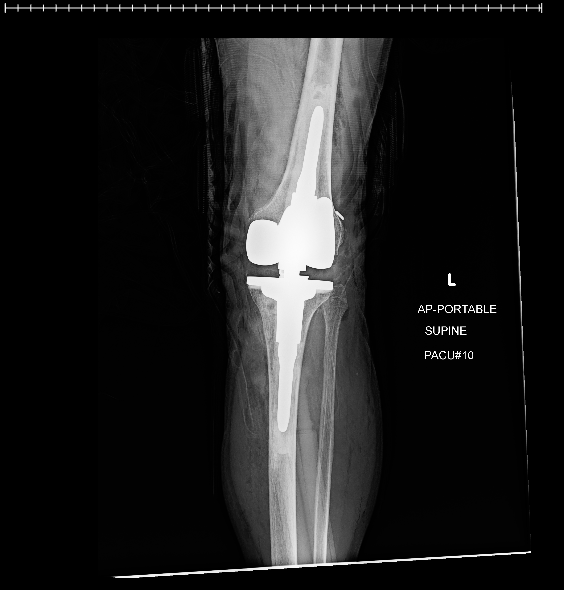

Pic!

Note the connection between the femur and tibia.

That is a hinge with a stop. the long projection into the bones distributes the forces over a larger area

(axial ? it isn't sheer, compression, or tension @shrpshtr325 )